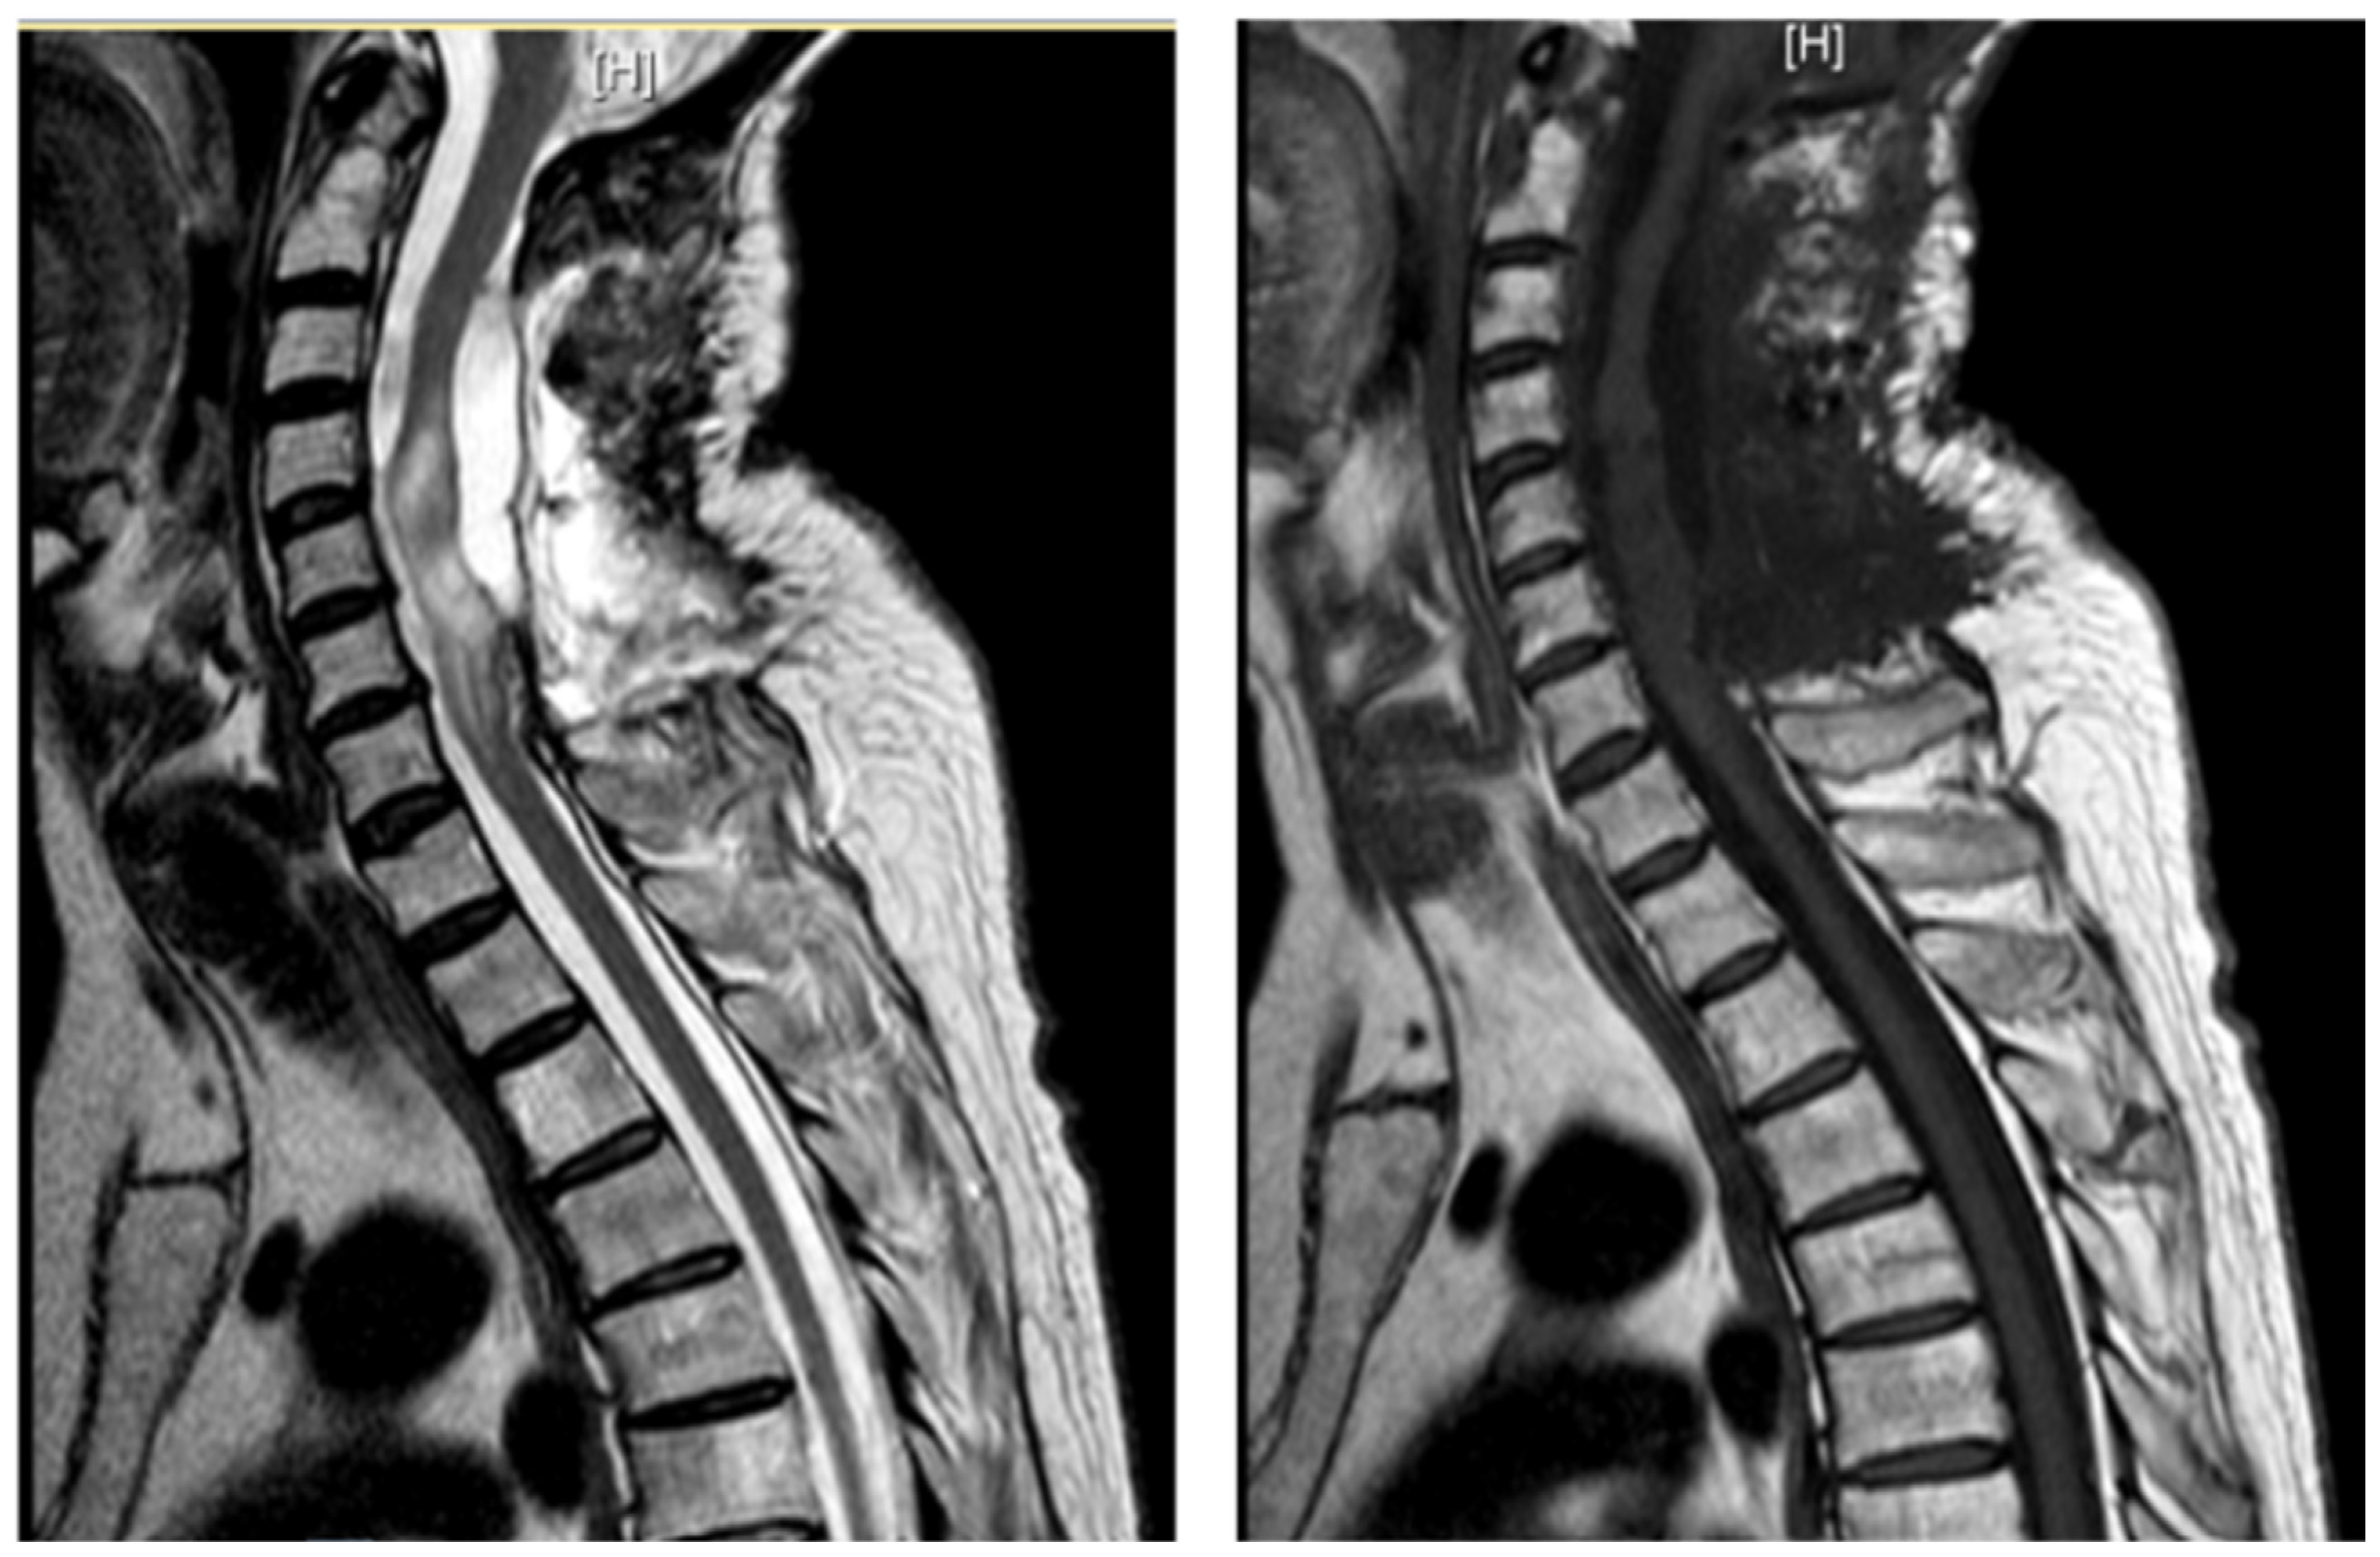

3.4.3. Case 3

3.4.4. Case 4

| Level | T12–L2 | C5–C6 | T7–T10 | T8–T9 | T8–T11 |

| Location | Intramedullary | Intradural | Intradural–Extradural | Intramedullary | Intradural |